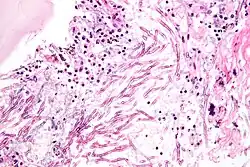

Lungengewebe eines an Aspergillose Erkrankten

Aspergillom – histologischer Schnitt

Mikroskopaufnahme eines histologischen Schnittes durch Lungengewebe mit pulmonaler Aspergillose

Die Fähigkeit der Gießkannenschimmel, auf vielen verschiedenen Substraten unter einem breiten Spektrum von Umweltbedingungen zu leben, führt dazu, dass einige Arten auch lebende oder tote Gewebe von Menschen oder Tieren bewachsen können. Der Befall von lebendem Gewebe ist der Auslöser verschiedener Krankheiten. Ein solcher Befall ist aber immer zufällig, da alle Aspergillus-Spezies eigentlich Saprobionten sind. Neben dem direkten Befall von Gewebe produzieren viele Aspergillus-Arten giftige oder allergene Sekundärmetabolite.

Infektionen durch Aspergillus-Arten entwickeln sich oft in den Lungen von Säugetieren oder Vögeln. Der bedeutendste Erreger in der Gattung ist Aspergillus fumigatus. Bei gesunden Organismen kann sich als akute Erkrankung ein Aspergillom bilden. Dies ist eine kugelige Kolonie in den Lungen oder den Nasennebenhöhlen, vergleichbar mit einem Pilzball, der sich in das Organ einnistet. Menschen sind vor allem dann gefährdet, wenn Lungenkavernen oder vernarbtes Gewebe aus vorhergegangenen Erkrankungen vorhanden sind, wie zum Beispiel nach einer Tuberkulose. Bei Nutztieren sind Aspergillome häufig.

Wachsen eingeatmete Aspergillus-Sporen in der Lunge aus und sind nicht auf eine kompakte Kolonie beschränkt, entwickelt sich eine akute Aspergillose. In der Lunge bilden sich Hyphen und anschließend Myzel, das schließlich über die Blutbahn im gesamten Körper streut. Es bilden sich Metastasen an den Organen und im zentralen Nervensystem. Bei erwachsenen Menschen mit intaktem Immunsystem kommen akute Aspergillosen nicht vor, bei Kindern sind sie sehr selten. Immunsupprimierte Patienten, zum Beispiel nach einer Knochenmark- oder Stammzelltransplantation oder AIDS-Patienten erkranken aber nicht selten daran. Die invasive Aspergillose ist eine gefährliche Infektion mit einer hohen Letalität im Bereich zwischen 50 % und 95 %.[17] Vor allem Vögel erkranken häufig an akuten Aspergillosen. Bei Küken von Haushühnern wird die Erkrankung Aspergillus-Pneumonie genannt und führt immer wieder zu Massensterben in Zuchtanlagen. Auch bei Wildvögeln treten immer wieder Epidemien auf und wurden unter anderem bei Afrikanischen Straußen (Struthio camelus) und Silbermöwen (Larus argentatus) beobachtet. Bei Papageien (Psittaciformes) treten durch Aspergillus verursachte Lungen- und Luftsackmykosen auf.[18] Unter Säugetieren sind Erkrankungen bei Lämmern häufig, bei Hausrind-Kälbern dagegen sehr selten. Epidemien traten bei Kaninchen und Meerschweinchen (Caviidae) auf. Bei Pferden (Equus) sind vor allem Luftsackmykosen gefürchtet. Diese werden zumeist durch Aspergillus fumigatus, aber auch durch andere Aspergilli oder Pilze der Gattungen Penicillium oder Mucor verursacht.[19]